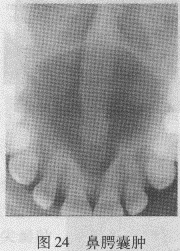

【解析】该图为上颌腭中线前方、左右中切牙牙根之间的心形低密度影,是比较典型的鼻腭管囊肿的X线表现。鼻腭管囊肿病变是一种起源于上颌鼻腭管(切牙管)内残余上皮的发育性囊肿。该囊肿又称为切牙管囊肿和鼻腭囊肿。病变位于上颌左、右中切牙牙根之间或后方,多呈心形或圆形低密度改变,病变边界清楚,周围有骨密质线围绕。囊肿可致两侧中切牙牙根分离和移位,但牙周膜和骨硬板连续。

(1)鼻腭囊肿:位于上颌中线,左、右中切牙牙根之间,呈心形或圆形低密度影(图24)。

(1)鼻腭囊肿:位于上颌中线,左、右中切牙牙根之间,呈心形或圆形低密度影。